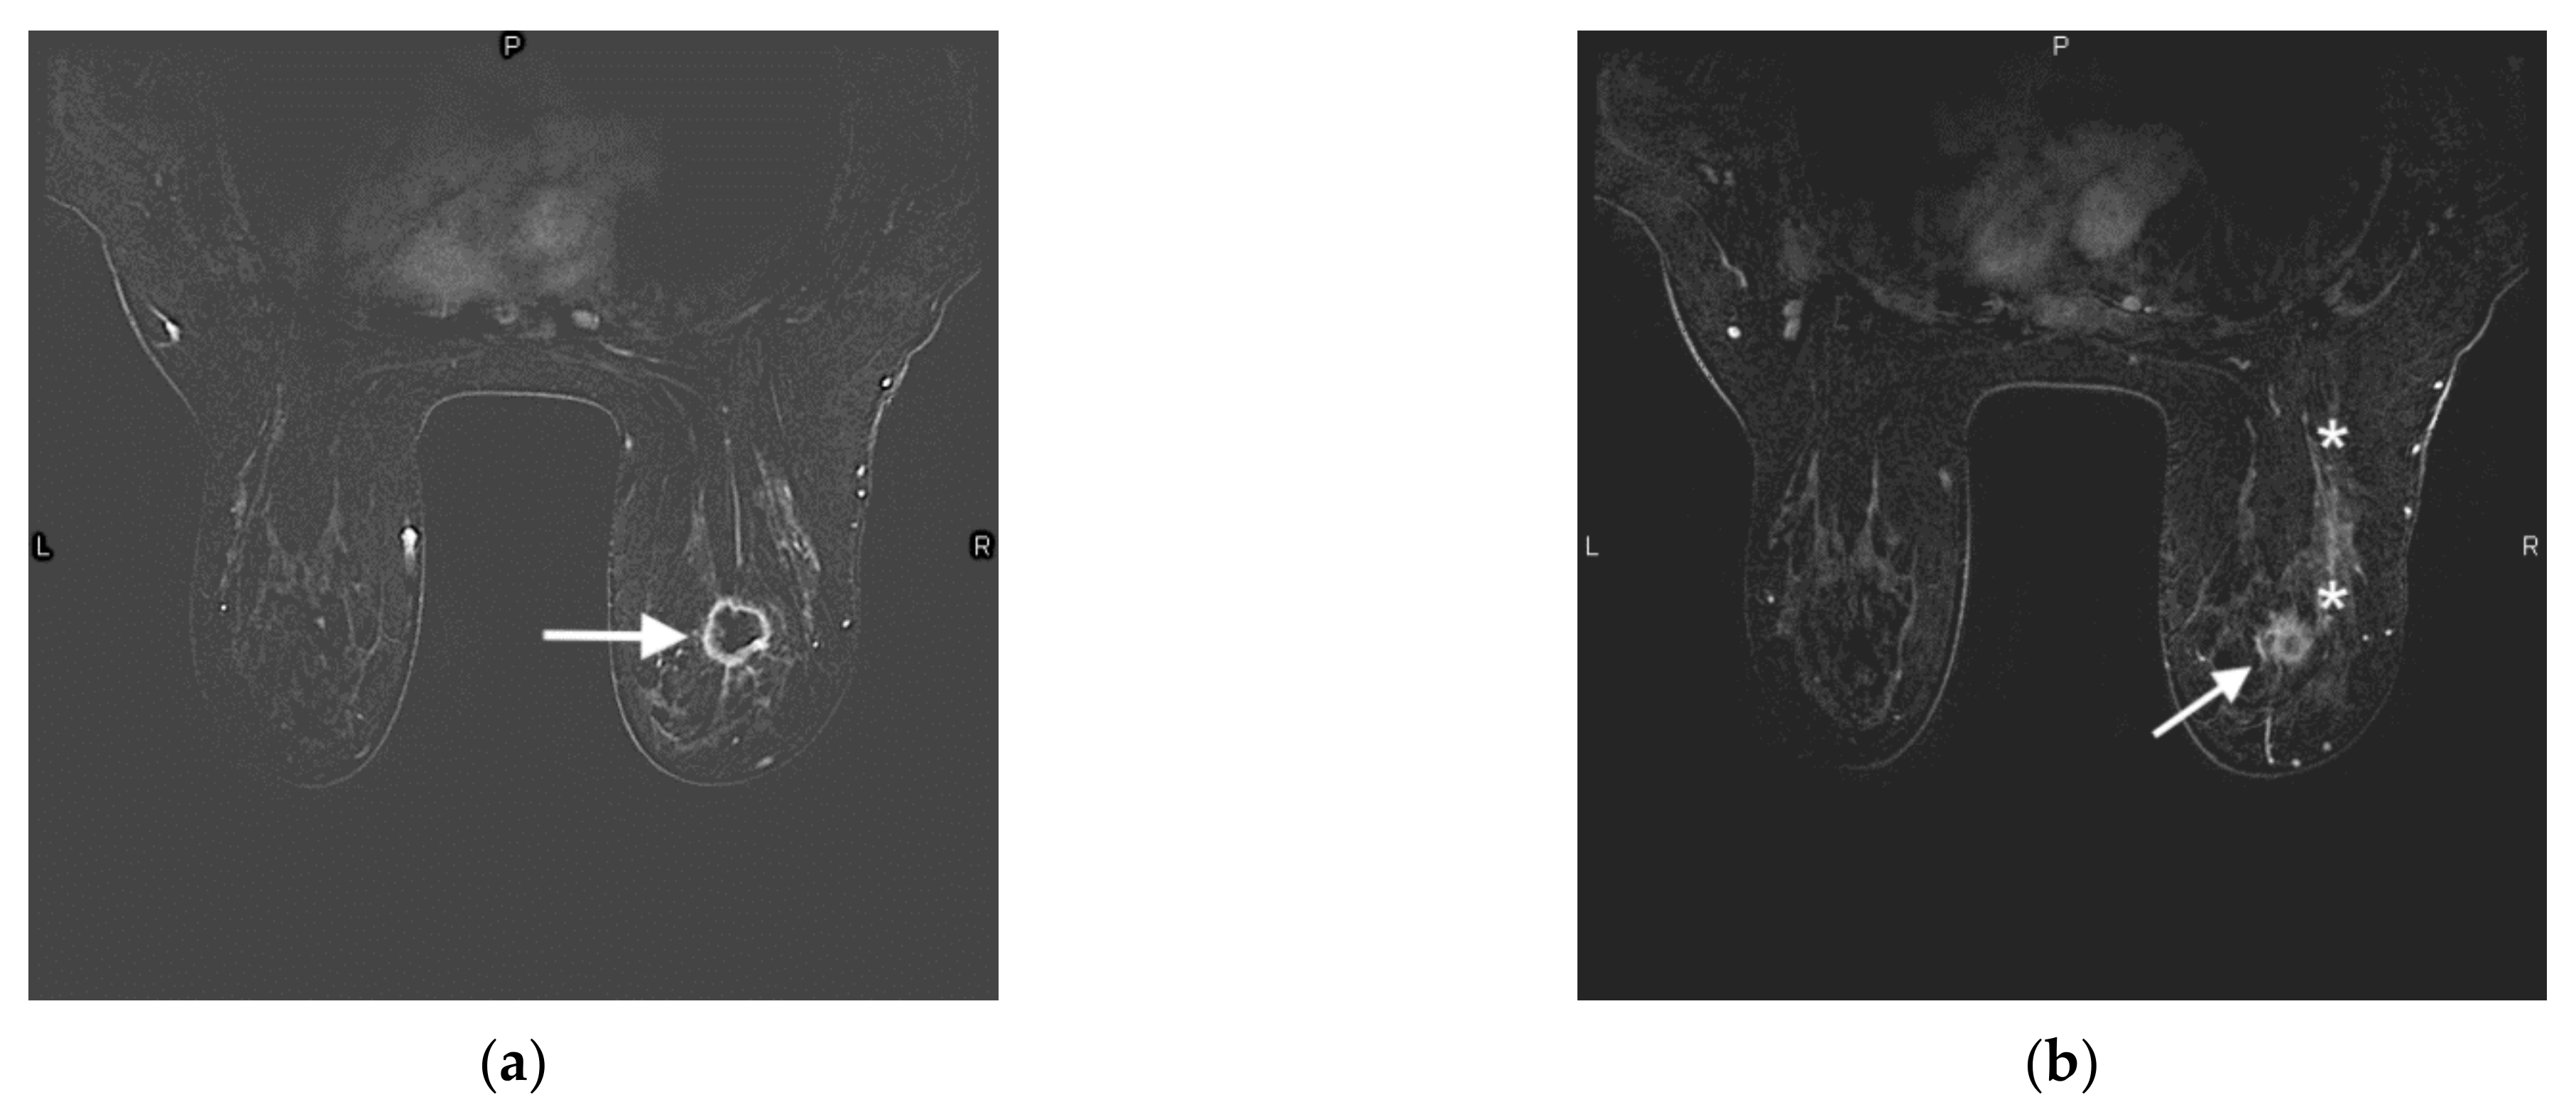

- Brennan, M.E.; Houssami, N.; Lord, S.J.; Macaskill, P.; Irwig, L.; Dixon, J.M.; Warren, R.M.; Ciatto, S. Magnetic resonance imaging screening of the contralateral breast in women with newly diagnosed breast cancer: Systematic review and meta-analysis of incremental cancer detection and impact on surgical management. J. Clin. Oncol. 2009, 27, 5640–5649. [Google Scholar] [CrossRef] [PubMed] [Green Version]

- Plana, M.N.; Carreira, C.; Muriel, A.; Chiva, M.; Abraira, V.; Emparanza, J.I.; Bonfill, X.; Zamora, J. Magnetic resonance imaging in the preoperative assessment of patients with primary breast cancer: Systematic review of diagnostic accuracy and meta-analysis. Eur. Radiol. 2012, 22, 26–38. [Google Scholar] [CrossRef] [PubMed]

- Benveniste, A.; Ortiz-Perez, T.; Ebuoma, L.; Sepulveda, K.; Severs, F.; Roark, A.; Wang, T.; Sedgwick, E. Is breast magnetic resonance imaging (MRI) useful for diagnosis of additional sites of disease in patients recently diagnosed with pure ductal carcinoma in situ (DCIS)? Eur. J. Radiol. 2017, 96, 74–79. [Google Scholar] [CrossRef] [PubMed]

- Kuhl, C.K.; Strobel, K.; Bieling, H.; Wardelmann, E.; Kuhn, W.; Maass, N.; Schrading, S. Impact of Preoperative Breast MR Imaging and MR-guided Surgery on Diagnosis and Surgical Outcome of Women with Invasive Breast Cancer with and without DCIS Component. Radiology 2017, 284, 645–655. [Google Scholar] [CrossRef] [Green Version]

- Lobbes, M.B.; Vriens, I.J.; Van Bommel, A.C.; Nieuwenhuijzen, G.A.; Smidt, M.L.; Boersma, L.J.; Van Dalen, T.; Smorenburg, C.; Struikmans, H.; Siesling, S.; et al. Breast MRI increases the number of mastectomies for ductal cancers, but decreases them for lobular cancers. Breast Cancer Res. Treat. 2017, 162, 353–364. [Google Scholar] [CrossRef] [PubMed] [Green Version]